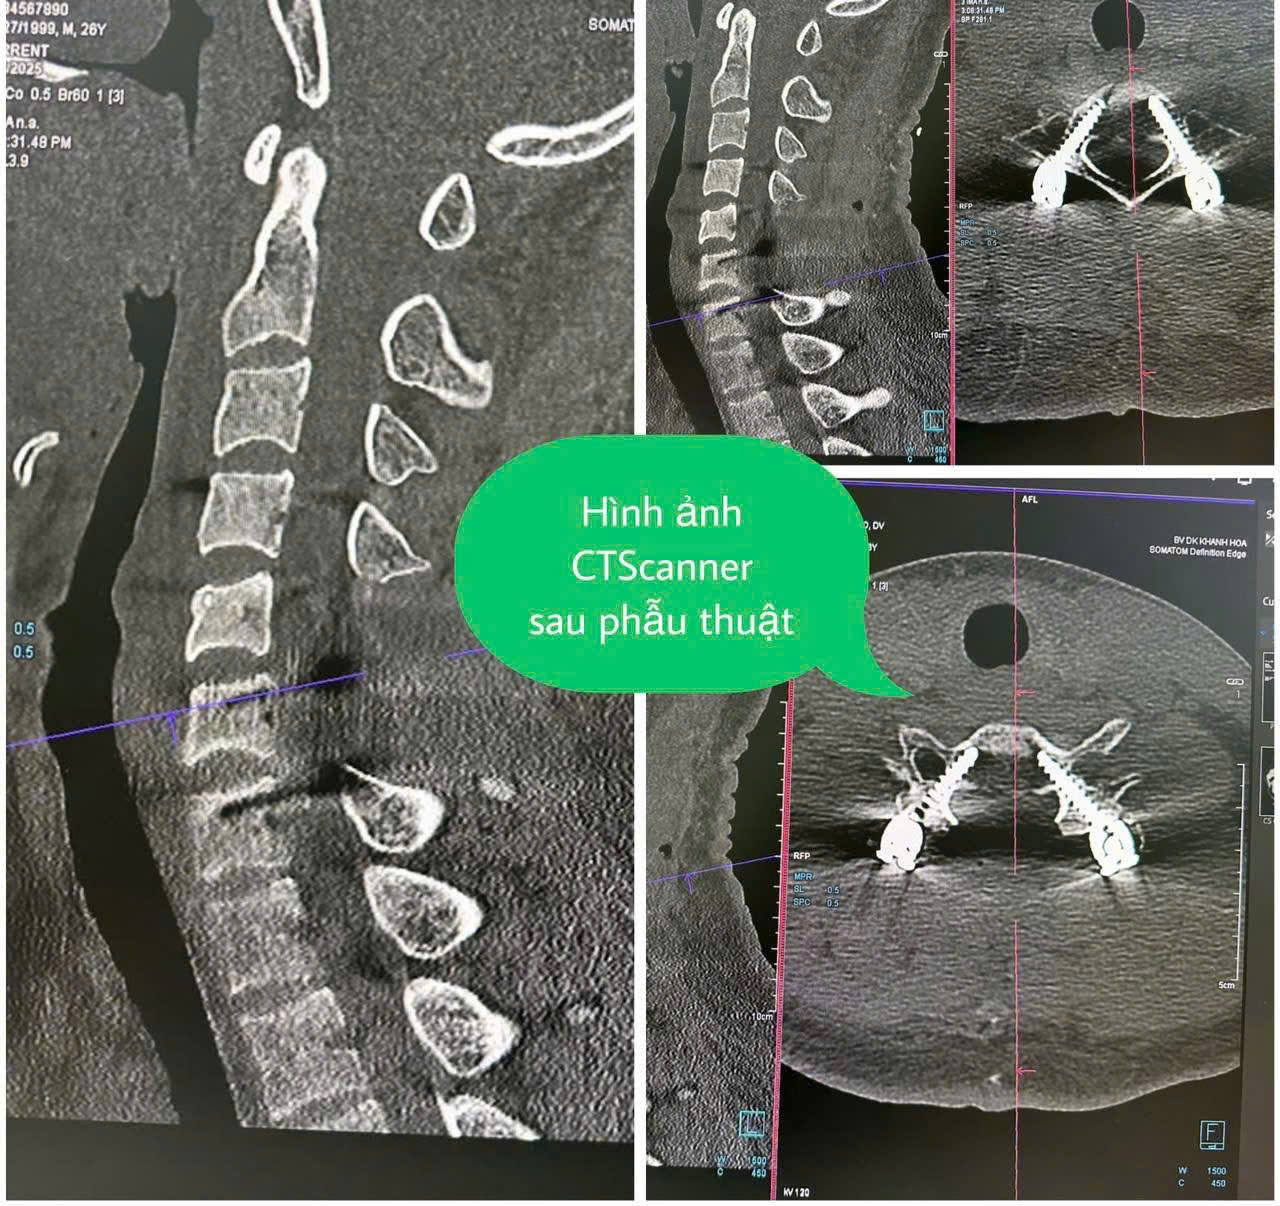

Được biết, từ năm 2016, đội đã được đầu tư xây dựng mới, đầu tư các trang thiết bị y tế thiết yếu phục vụ cho nhiệm vụ quân sự, quốc phòng và khám, chữa bệnh bảo hiểm y tế, như: Máy X-quang kỹ thuật số; máy CT Scanner 32 lát cắt; máy nội soi tiêu hóa; máy siêu âm 4D; máy sinh hóa tự động; buồng ôxy cao áp; ghế răng; máy nội soi tai mũi họng; hệ thống máy đông y, vật lý trị liệu... Hằng năm, các y, bác sĩ của đội thường xuyên được đi học tập nâng cao trình độ chuyên môn nghiệp vụ ở tuyến trên như: Bệnh viện Bạch Mai, Bệnh viện Trung ương Quân đội 108, Bệnh viện Quân y 175, Bệnh viện Quân y 87, Bệnh viện Đa khoa tỉnh Khánh Hòa... Nhờ đó, Đội Điều trị 486 đã nâng cao chất lượng khám, chữa bệnh, đảm bảo tốt công tác chăm sóc sức khỏe cho quân và dân trên địa bàn.